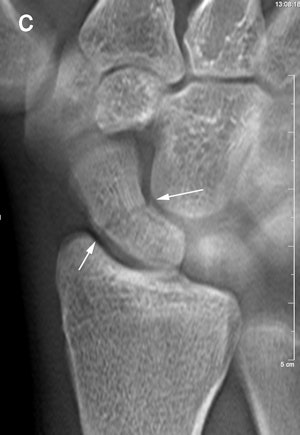

Up to now, digital x-ray tomosynthesis has not been considered for this application. The technology has the ability to demonstrate cortical fractures and fractures of the trabecular bone with some degree of displacement, Geijer wrote. In that respect, its performance is similar to CT.

The experience also taught the participating radiologists that detecting fractures with tomosynthesis is somewhat different than with conventional radiography and CT. Fracture detection is mainly based on edge disruption with tomosynthesis because the structure of the medullary bone is blurred and not as distinct as in CT, Geijer noted.

The tomosynthesis sections had a "nonprecise" thickness, with a sharp resolution at the image center, and increasing "fuzziness" apparent toward the image edges.

Fracture detection was aided on the lateral borders by the ability to visualize the scaphoid bone cortex. Fractures could also be appreciated on the most dorsal and palmar sections because of good contrast between the bone and surrounding soft tissue or medullary bone, he wrote.

Image artifacts with tomosynthesis included increased noise during scaphoid imaging and the superimposition of adjacent cortical lines and carpal joint structures.

"The way a fracture is seen with tomosynthesis is thus different from both radiography and CT," he wrote.